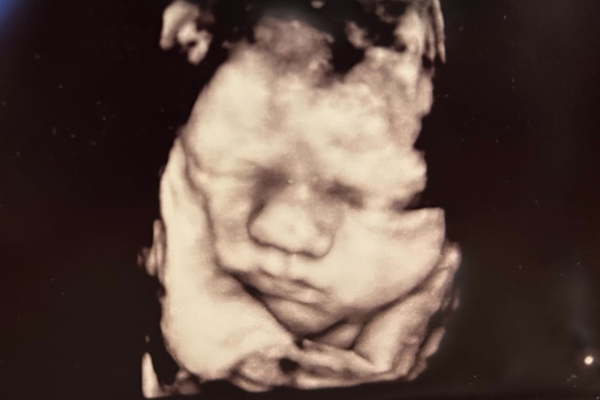

Gravid uge 37

38. Graviditetsuge

Uge 37+0 – 37+6

Dit barn måler nu cirka 48 cm og vejer 3000 gram. Barnet bruger de sidste uger på at opbygge et godt fedtlag og tager derfor stadig på. Efter fødslen betyder vægten noget for evnen til at regulere temperaturen. Et barn der bliver født i uge 37+ er både klar til at spise ved dit bryst og har som regel ikke brug for assistance, hverken til vejrtrækningen eller til at holde varmen.